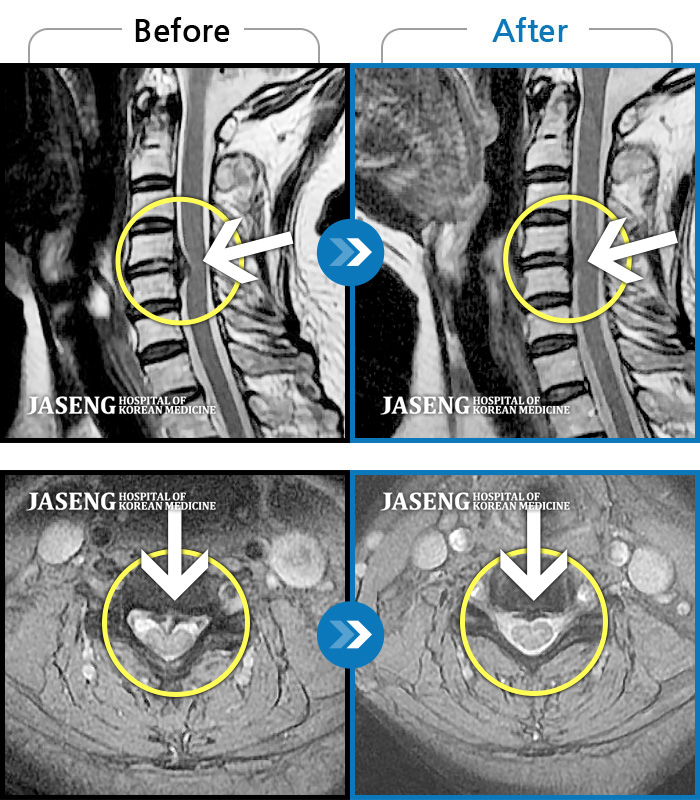

자생 비수술 한방통합치료 후

터진디스크가 흡수된 모습

비수술 치료만으로

터진 디스크 흡수

Before

After

왼쪽 목부터 견갑골 안쪽까지 아프고 왼팔을 올릴때 팔부터 손 끝까지 저린감이 내려간다.

2024.04.01 ~ 2024.12.13

목통증, 왼쪽 팔저림, 두통, 잇몸통증까지 심해 일상생활 불가

2022.08.20 ~ 2024.02.24